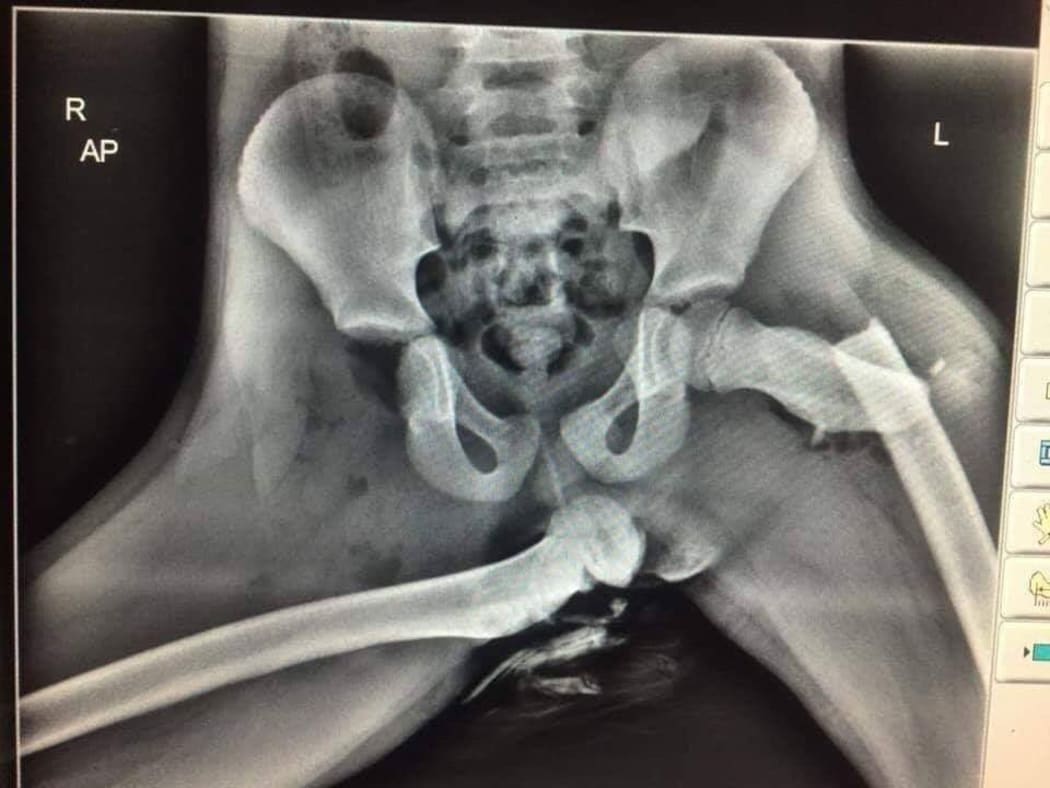

La radiographie qui vous montre pourquoi il ne faut pas mettre ses pieds sur le tableau de bord https://www.aplusglass.com/radiogra [...] u-de-bord/ Message cité 3 fois Message édité par ledenez le 22-11-2025 à 21:04:06 |

hisvin | Il suffit de leur montrer un crash test. De mémoire, ils sont fait à 50 km/h. (En fait, 64 en vérifiant.) |